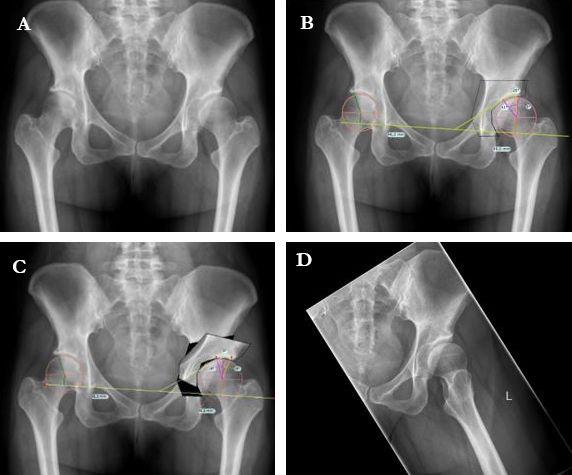

The clinical articles in this issue address a spectrum of reconstructive and preoperative challenges. The management of tibial plateau fractures, encompassing diagnostics, classification, and treatment, is complemented by an analysis of mechanical alignment alternatives, from anatomical to kinematic alignment in total knee arthroplasty. Attention then turns to the hip, with surgical guidance on minimally invasive periacetabular osteotomy for adult hip dysplasia, alongside a critical appraisal of total hip arthroplasty planning, examining the limits of X-ray and the contribution of CT-scan imaging.